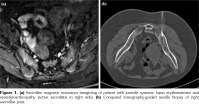

A 16-year-old Syrian female patient was admitted to our hospital with low-back pain present for two months. She was born by vaginal delivery at 39 weeks as the second child of consanguineous parents (first cousins). She had initially presented to a local medical center with fever, rash, fatigue, oral ulcers and pancytopenia a year before. She was diagnosed with SLE. Prednisolone (1 mg/kg) and hydroxychloroquine therapy was administered. One year later, she was referred to our hospital due to complaints of low-back pain worsening in the morning and after a long resting period during the last two months. She also suffered from morning stiffness lasting two-three hours and heel pain. On physical examination, Flexion, ABduction, External Rotation test and sacroiliac compression tests were all positive. She had tenderness in sacroiliac joints (SIJs) and heels. Schober test result was 5 cm. With these findings, she was hospitalized for a detailed evaluation. In laboratory work-up, baseline complete blood count, biochemical tests, and complete urinalysis were normal. Erythrocyte sedimentation rate was 43 mm/hour and C-reactive protein was 9.4 mg/L. The homogenous nucleolar antinuclear antibody pattern was found to be positive at 1/320 titer. Anti-double stranded deoxyribonucleic acid was also positive. Anti- cardiolipin and anti-β2 glycoprotein antibodies, lupus anticoagulant were all negative. She had normal levels of complement 3 and 4. She underwent sacroiliac and thoracolumbar magnetic resonance imagining (MRI). Sacroiliac MRI revealed active sacroiliitis in the right side based upon bone marrow edema in short tau inversion recovery sequences and increased enhancement in post contrast sequences (Figure 1a). However, thoracolumbar MRI was normal. Human leukocyte antigen (HLA)-B27 was negative. Since she used prednisolone during one year period without any calcium replacement, dual energy X-ray absorptiometry (DXA) was performed. DXA showed L2-L4 Z-score: -2.6 standard deviation (SD), neck of hip Z-score: -2.5 SD. Anti-resorptive treatment including pamidronate, calcium and vitamin D were administered. Steroid treatment was tapered to 5 mg per day. She had a low socio-cultural level and used immunosuppressive agents approximately for one year. Therefore, she was screened for presence of tuberculosis (TB). Tuberculin skin test was 0 mm and computed tomography (CT) of the thorax was normal. Finally, CT-guided needle biopsy of the right SIJ was performed and histopathological examination revealed chronic inflammation (Figure 1b). Bacterial and TB cultures, as well as TB polymerase chain reaction were all negative. She was diagnosed with juvenile SpA after exact exclusion of differential diagnoses. Subcutaneous methotrexate (15 mg/m2/weekly), folic acid supplement, and non-steroid anti-inflammatory drug were started. Her symptoms responded to this treatment positively. A written informed consent was obtained from the legal guardians of the patient.